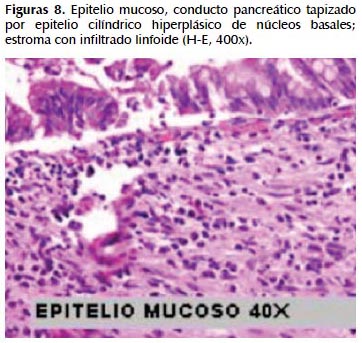

La alteración fundamental en este caso es la presencia de marcada dilatación de los conductos pancreáticos (Figuras 6, 7, 8, 9, 10 y 11) con variable hiperplasia de los conductos menores periféricos.

Los quistes están limitados por células ductales altas, algunas mucinosas, en su mayor extensión dispuestas en una fila. De manera focal se ve proyecciones papilares del epitelio y también focos de erosión con reacción inflamatoria, exudado linfocitario y formación de tejido de granulación.

El resto del parénquima pancreático muestra múltiples focos de autolisis y variable hiperplasia de los ductos.